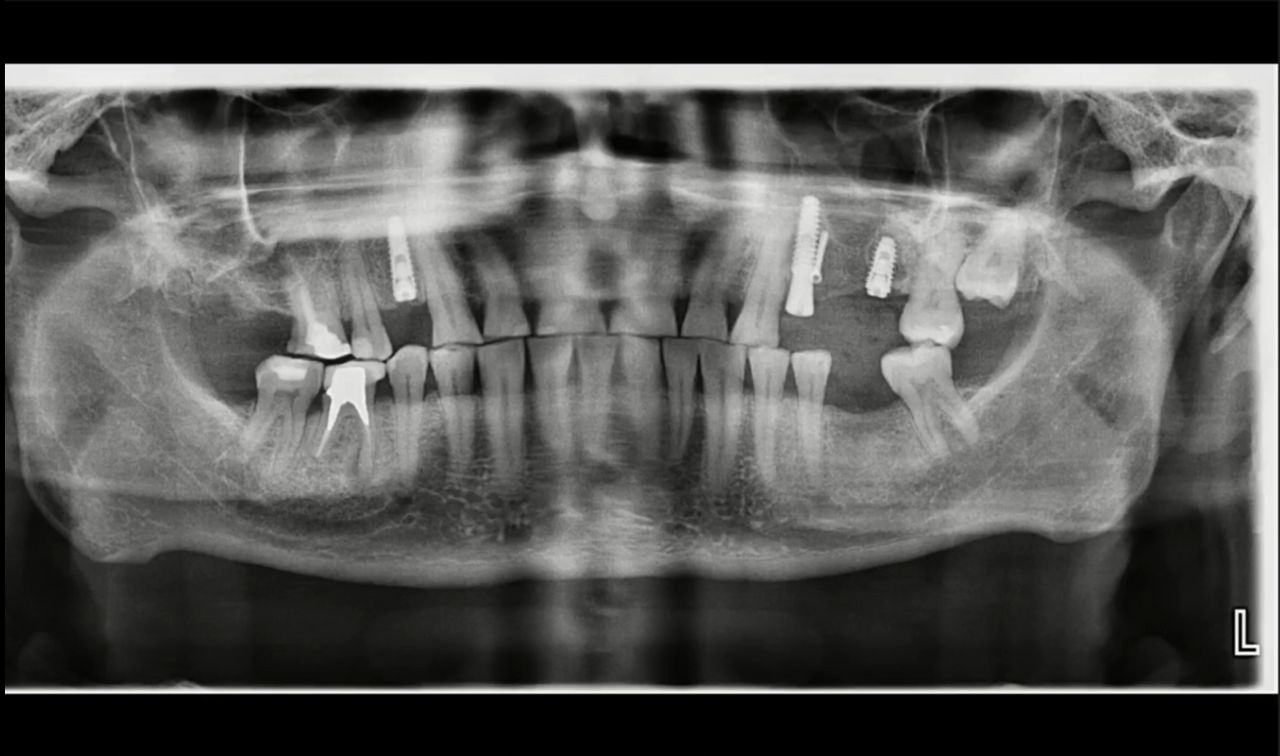

Материалы и методы при при заборе аутогенной костной ткани